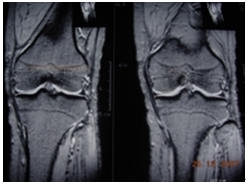

膝关节慢性滑膜炎图片